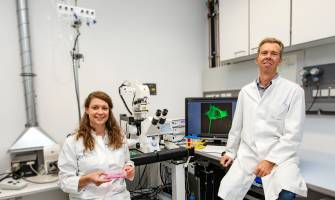

Biowissenschaften - Pharmakologie - 01.09.2020

Forschungsgruppe unter MHH-Leitung findet neuen Therapieansatz durch Behandlung eines Serotonin-Rezeptors Dr. Josephine Labus und Evgeni Ponimaskin im Labor des MHH-Instituts für Neurophysiologie. Auf dem Monitor ist eine Zelle mit dem pathologischen Tau-Protein zu sehen Copyright: Karin Kaiser / MHH Stand: 01.